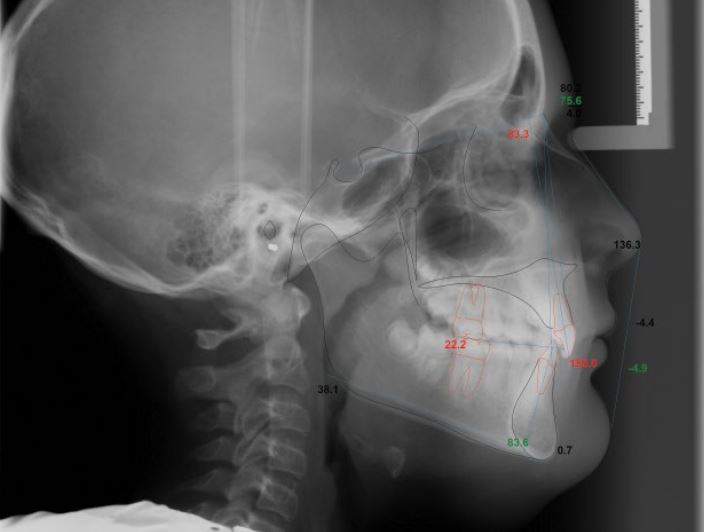

Nền xương hạng I, góc mặt phẳng hàm dưới hơi mở, trục răng cửa hàm trên và hàm dưới dựng đứng, cắn sâu và chen chúc răng cửa dưới.